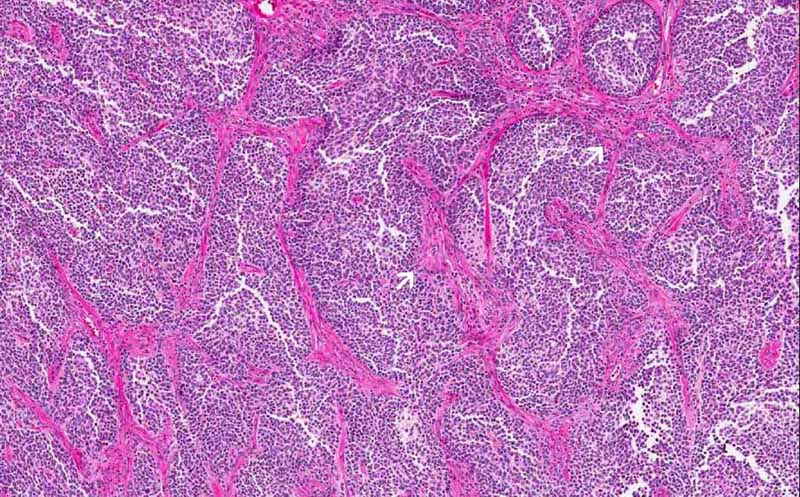

2: In this area, there are many pink

fibrovascular septa in between the tumor cells. When the leptomeninges

are involved by the tumor cells, the entrapped fibrovascular component

can give this histologic pattern. |